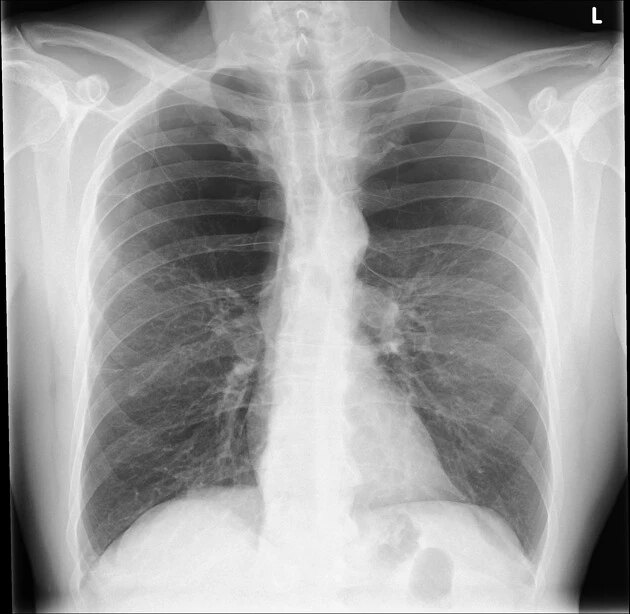

肺气肿 病理上分为小叶中央型,全小叶型和间隔旁型三种类型.

小叶中央型肺气肿图1在ct图像上,肺气肿表现包括局灶的或区域性的密度

肺气肿胸片

肺气肿x线表现

肺气肿x线图片

肺气肿图片

肺气肿图片高清图片